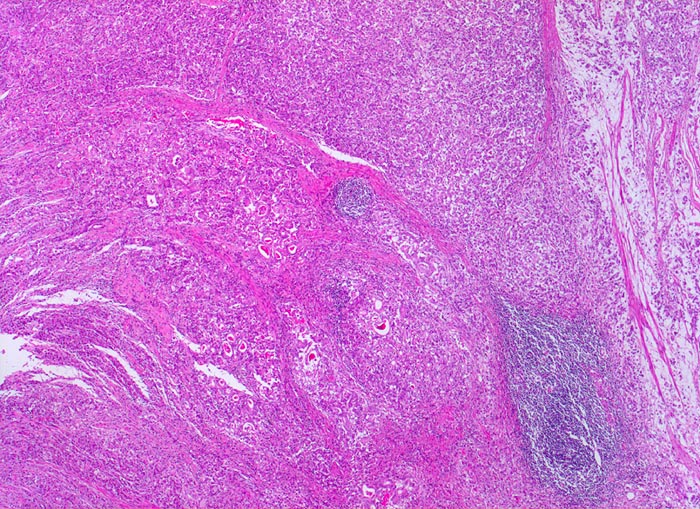

• Gewebsfragment aus gastroösophagealem Übergang.

• Das unscharf begrenzte Karzinom breitet sich diffus in der gesamten Magenwand und in der Ösophaguswand aus bis in des periösophageale und subseröse Fettgewebe.

• Ein Grossteil des Tumorinfiltrats besteht aus einzeln oder in kleinen Gruppen liegenden Zellen mit intrazytoplasmatischen Schleimvakuolen, die teilweise den Kern verdrängen (Siegelringzellen): diffuser Typ des Magenkarzinoms nach Lauren.

• Nur vereinzelt Drüsenbildung.

• Lymphgefässeinbrüche.